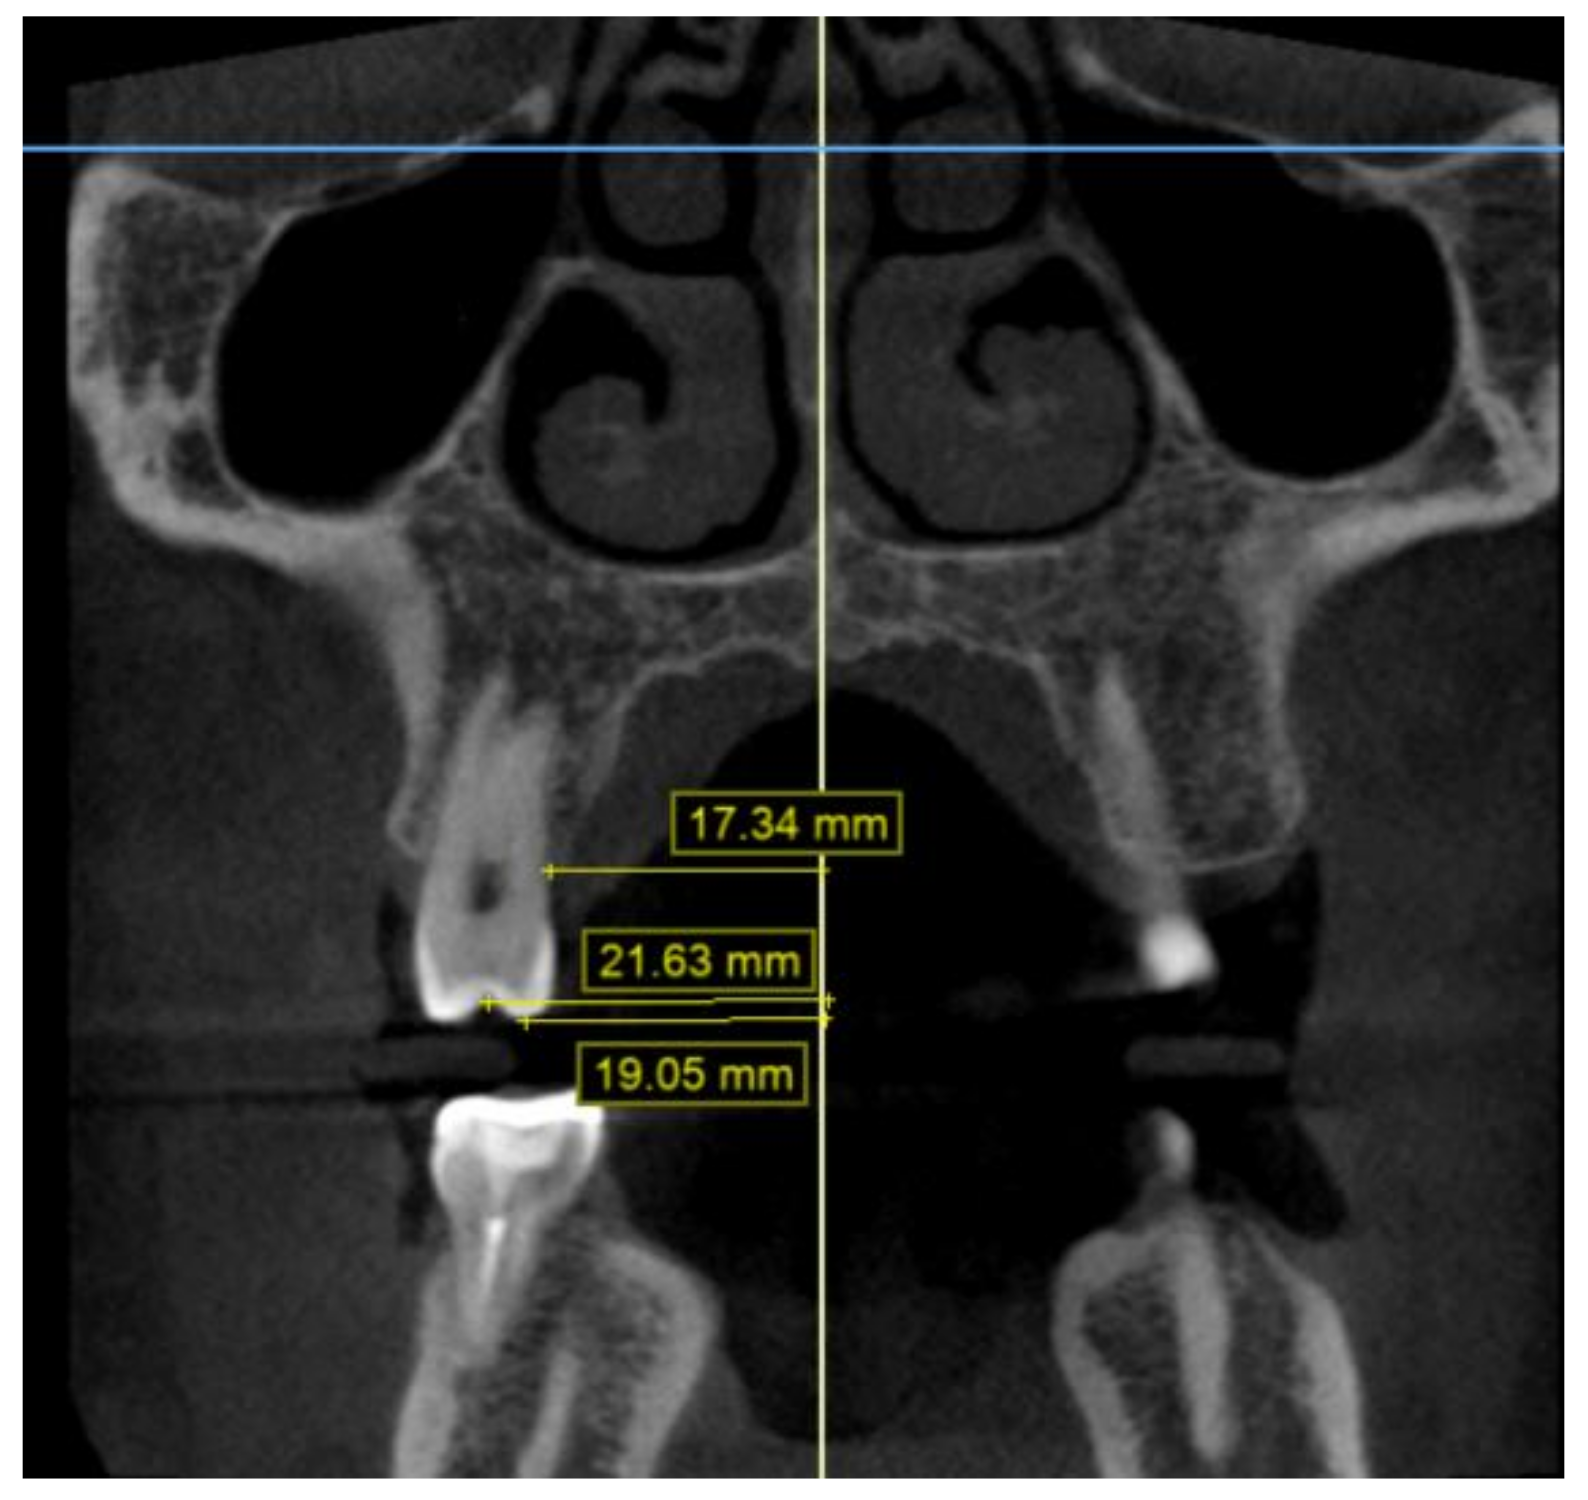

2.2. Methodology of Measurements

4.5. Transverse Measurements on CBCT Scans versus Casts